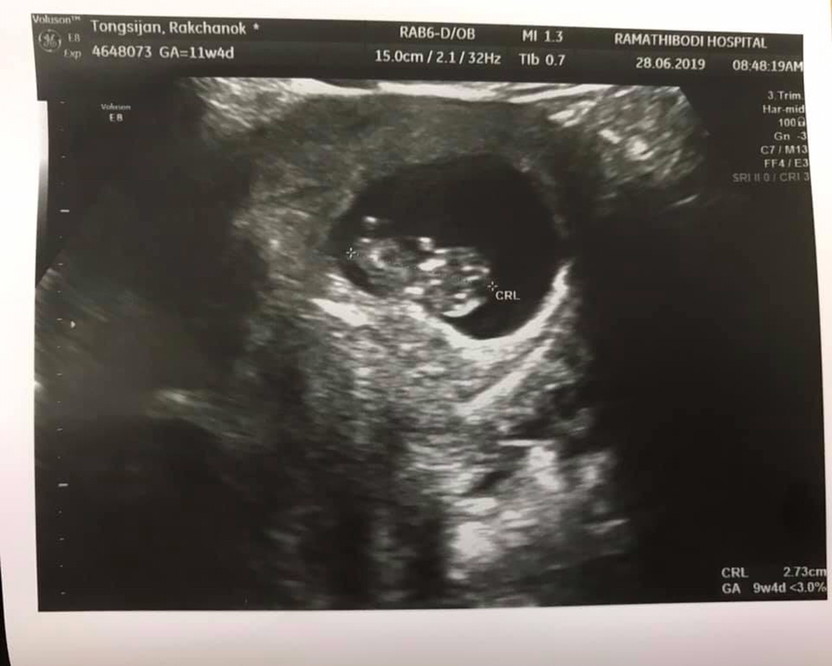

11 w 4 d ค่ะ